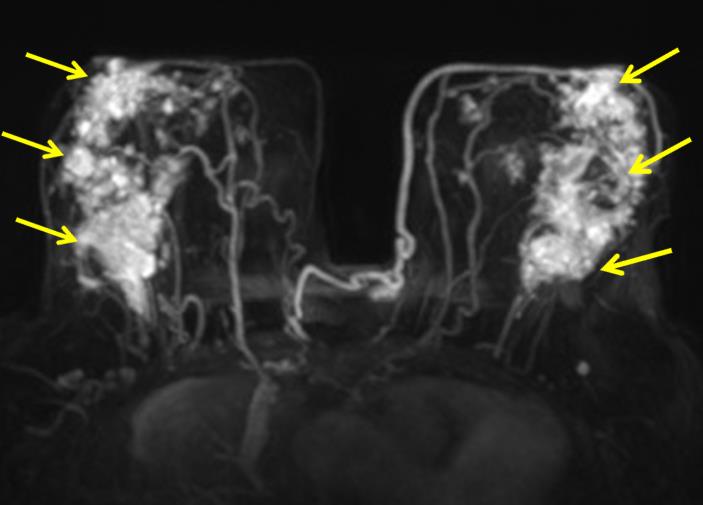

The most common cause of skin metastases in adult women is primary breast carcinoma, which comprises about 70% of cases [1]. Skin metastases have non-specific clinical appearances, making it challenging to differentiate them from other benign conditions [1]. We present a case of a 52-year-old female with type II diabetes and a three-month history of refractory skin lesions who did not respond to anti-inflammatory treatment. The patient subsequently complained of a right breast lump, evaluation of which led to the diagnosis of bilateral synchronous invasive lobular carcinoma.